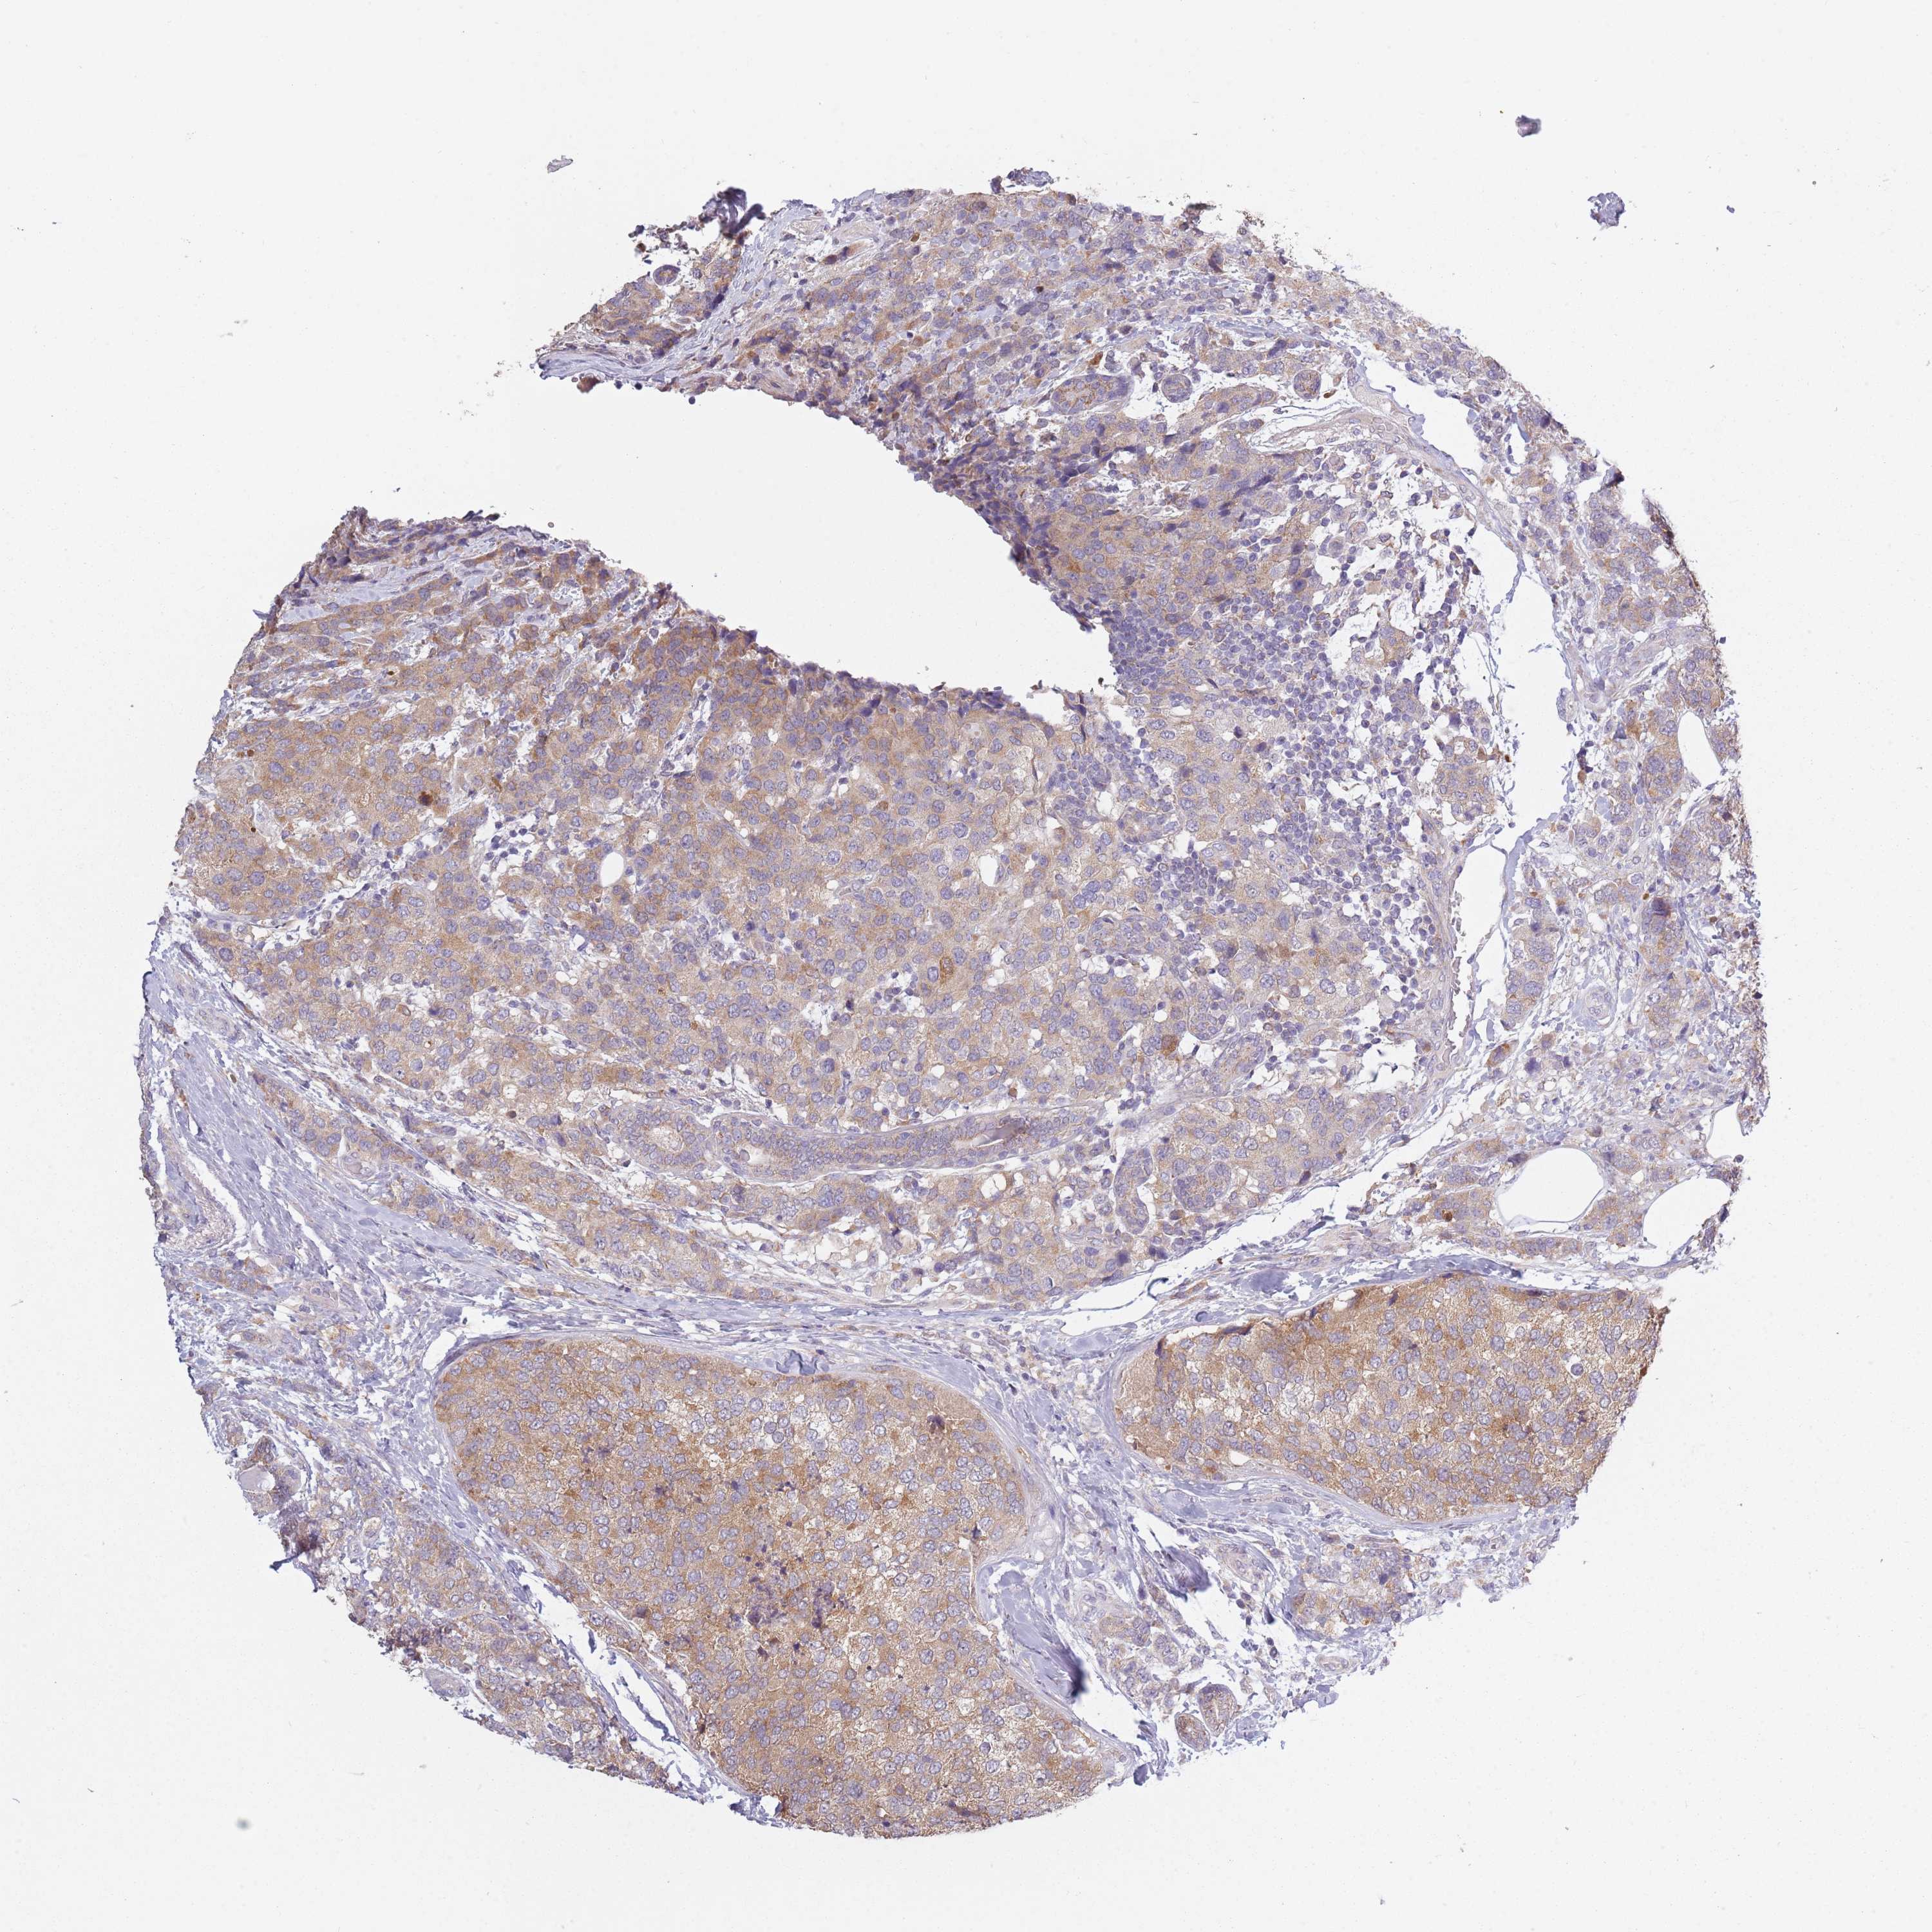

BRCA TCGA BRCA VALIDATION PROTEIN EXPRESSION